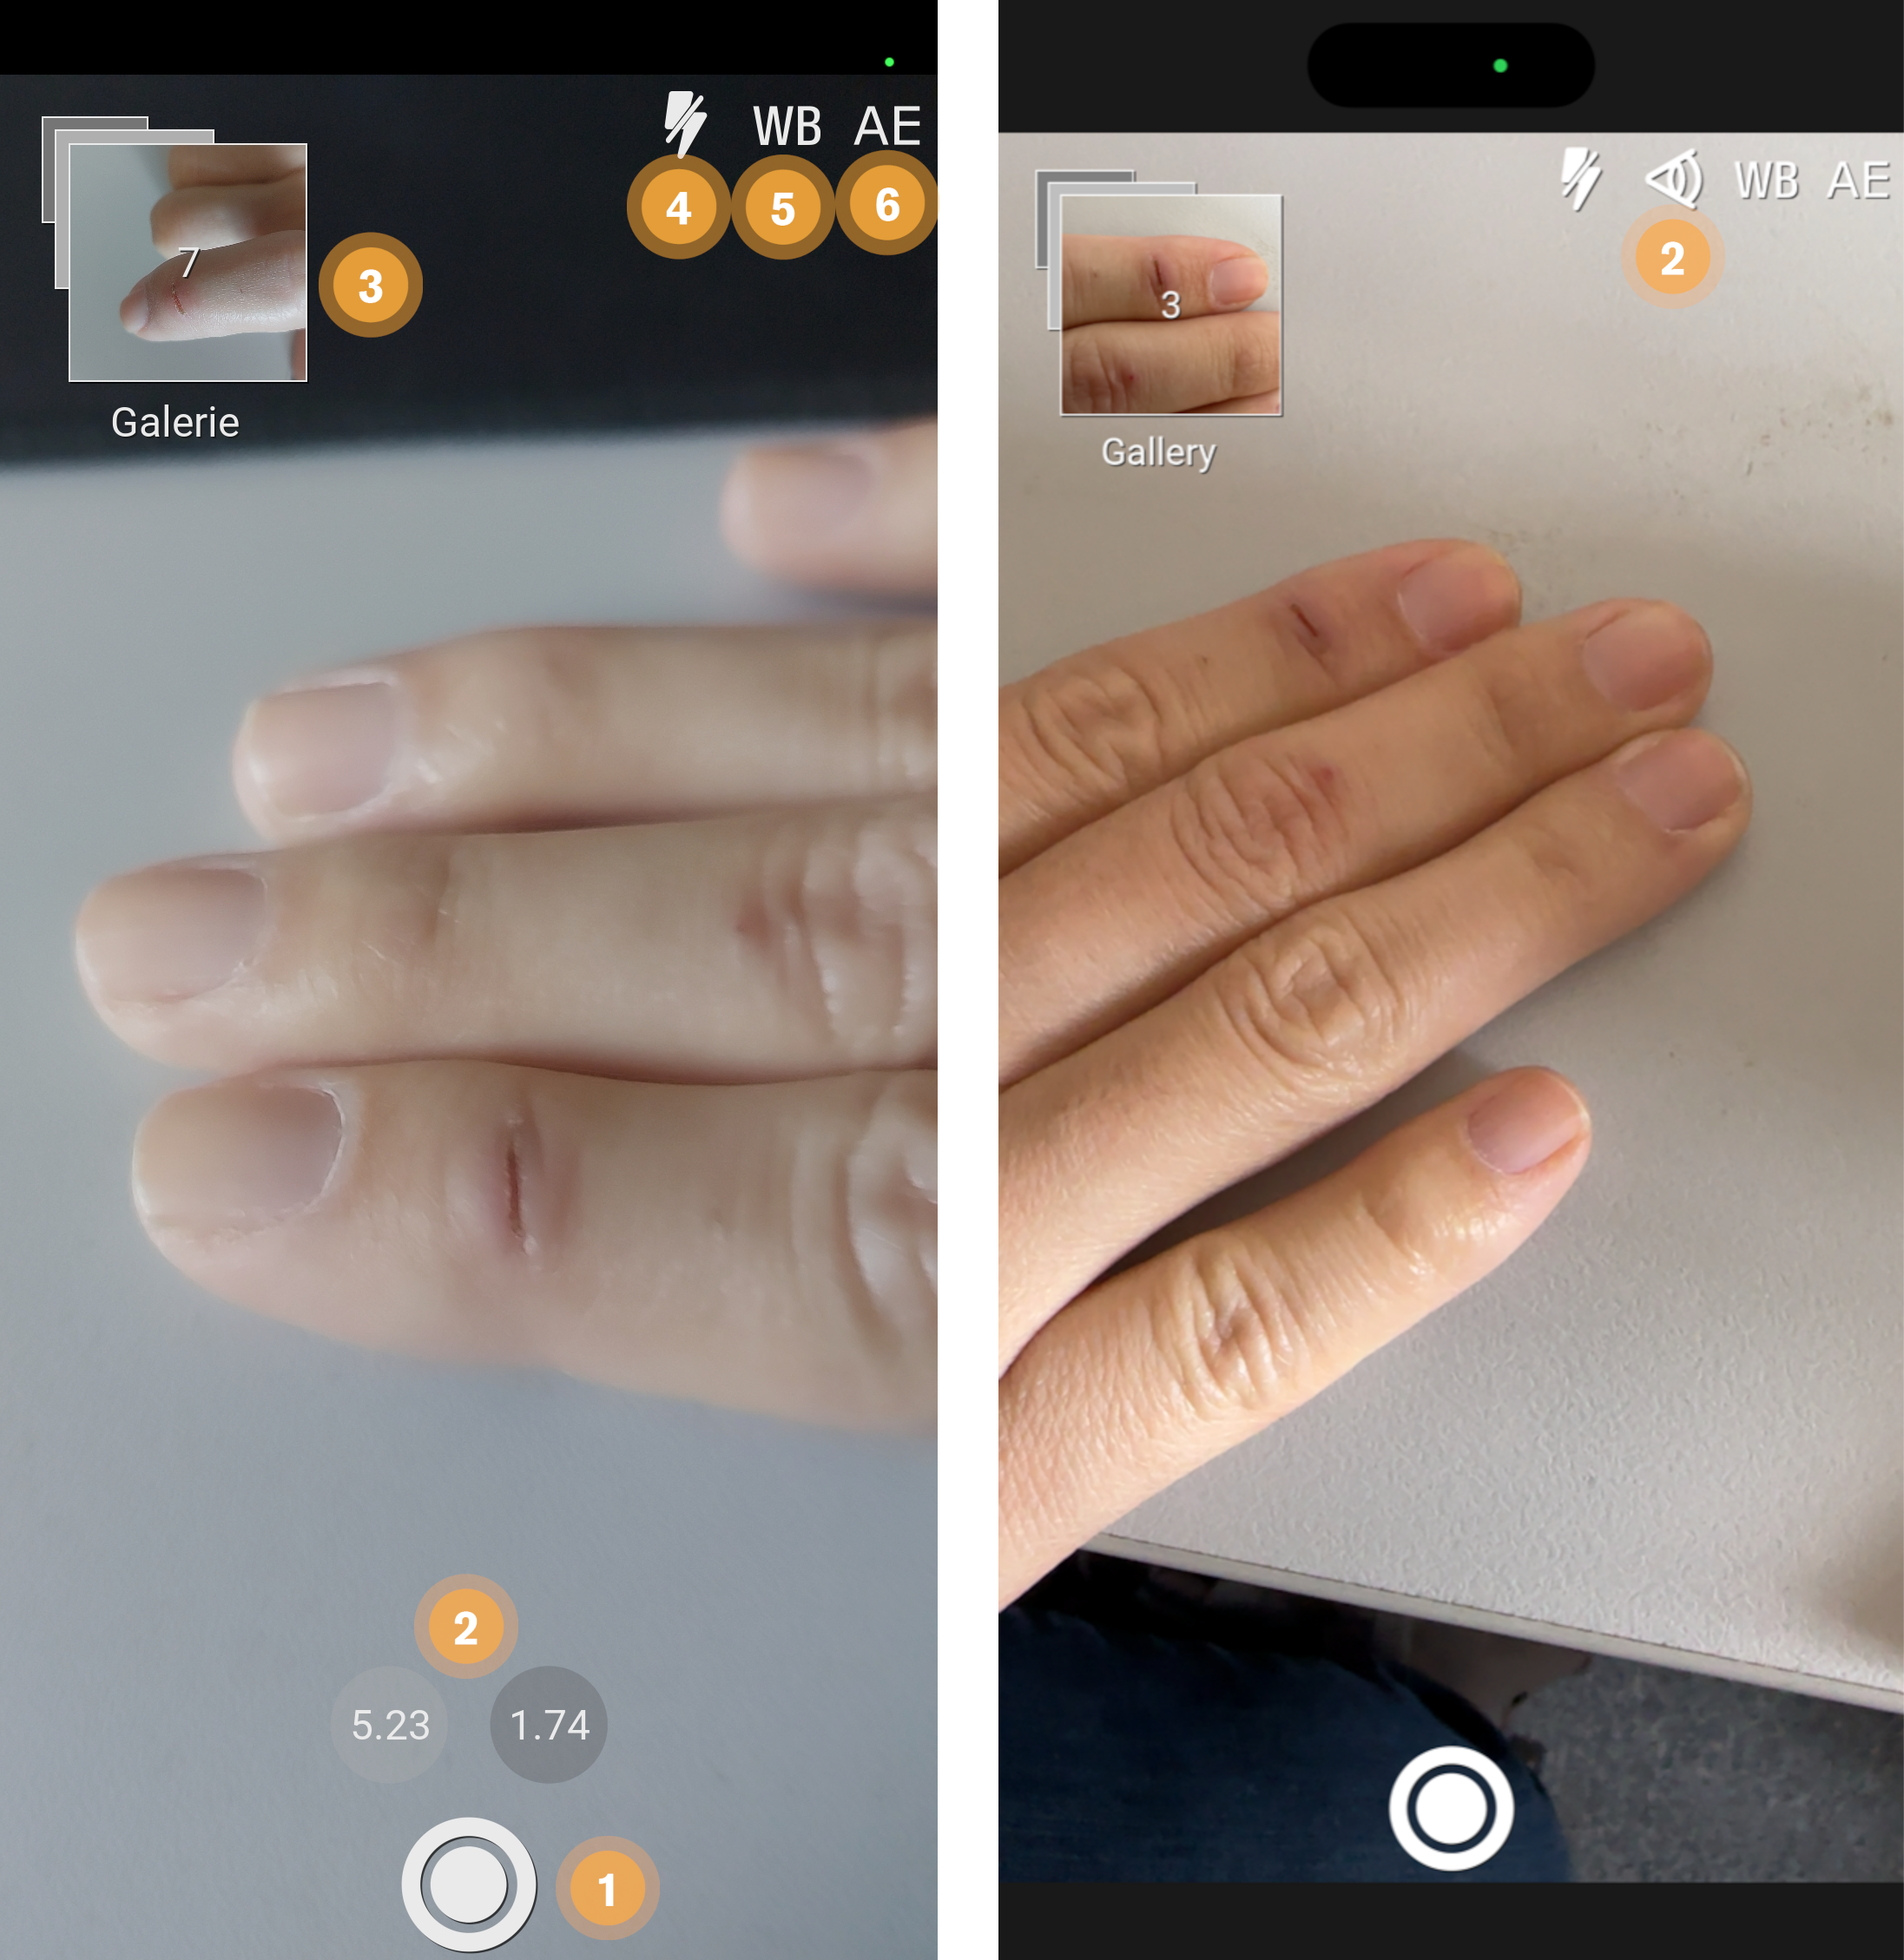

Aufnahme von Bildern zur Wunddokumentation. Versand der Aufnahme als DICOM Datei an ein PACS inkl. aller notwendigen Meta-Informationen

13.2. Foto Nachrichten

Neben Text, können auch Bilder an Kontakte versendet werden. Dies ist möglich durch einen Klick auf das Fotokamera-Symbol, welches sich links neben dem Textfeld befindet(siehe Chat).

Obige Abbildungen veranschaulichen folgende Funktionen:

-

Mit diesem Button können Sie von der Fotoaufnahme-Vorschau zurück zum Chat-Verlauf zurückkehren.

-

Dieser Button löst eine Aufnahme aus und versendet diese an Ihren ausgewählten Kontakt. Darauf befinden Sie sich wieder innerhalb des aktualisierten Chat-Verlaufs.

|

Bei Fotonachrichten erfolgt kein Zugriff auf den privaten Fotospeicher oder die -galerie des Gerätes. Die Fotos werden nur mRay intern verwaltet und gespeichert. |